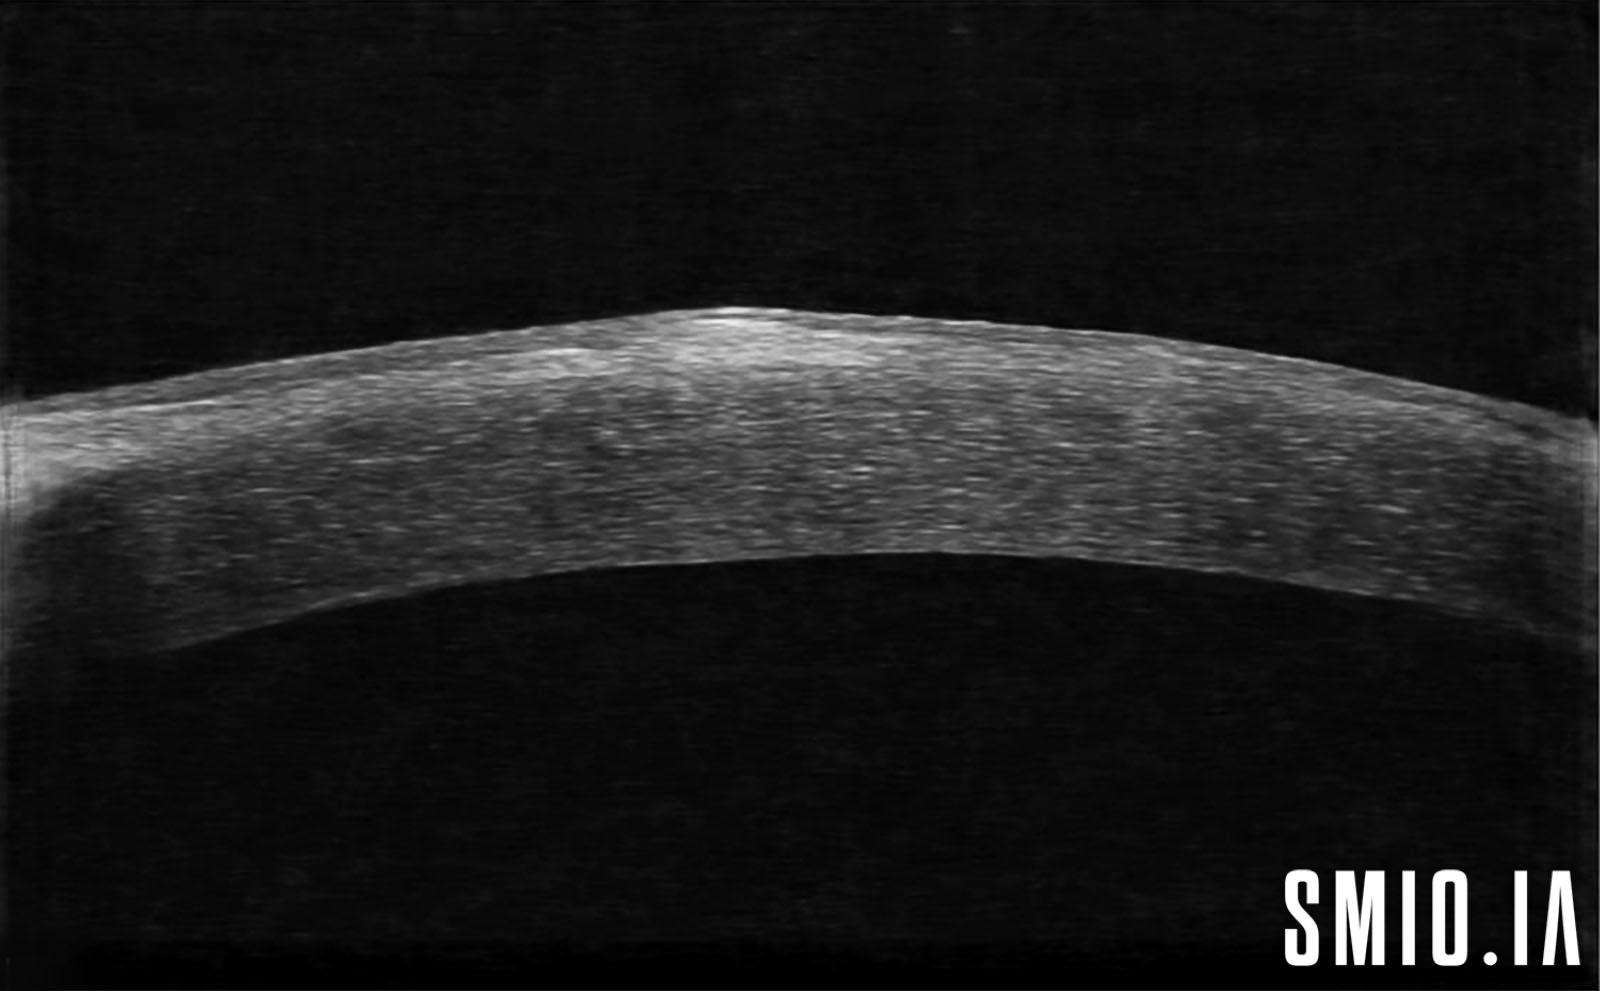

Description: La dégénérescence nodulaire de Salzmann chez une femme de 76 ans qui consulte pour la sécheresse oculaire et acuité visuelle basse, elle a également des cicatrices sous-épithéliales associées, la dégénérescence nodulaire de Salzmann est une condition lentement progressive dans laquelle des nodules gris-blanc bleuâtres mesurant 1 à 3 mm sont vus à La cornée à la couche de Bowman, généralement bilatéral. Ces nodules élevés peuvent être situés près du limbe ou dans la cornée à la mi-périphérie

Appareil d'imagerie: Huvitz HIS-5000U-Canon80D Optol Revo SOCT Copernicus